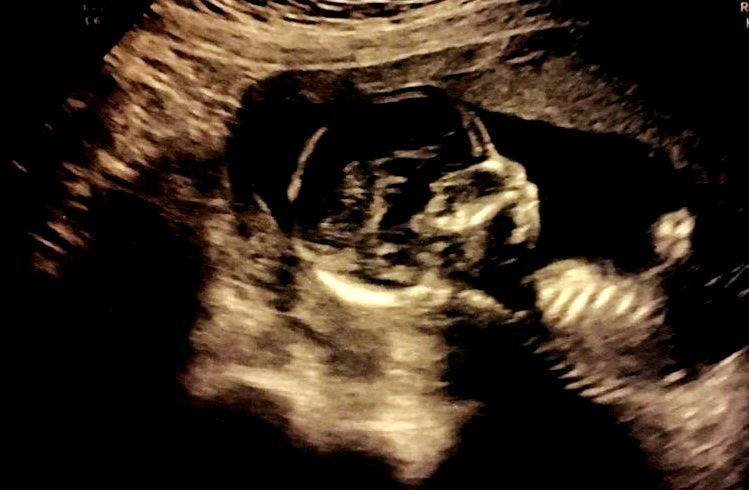

생명에 대해서 살펴본 적이 있는가. 그래도 지구 위에서는 사람이 아주 진화된 생물이고 지구를 지배하는 생명이다. 그런데도 엄마의 조그마한 태 속에서 아주 작은 물속에서 잉태되고 태어날 준비를 한다.

엄마의 바다.png

[엄마의 바다, 2018]